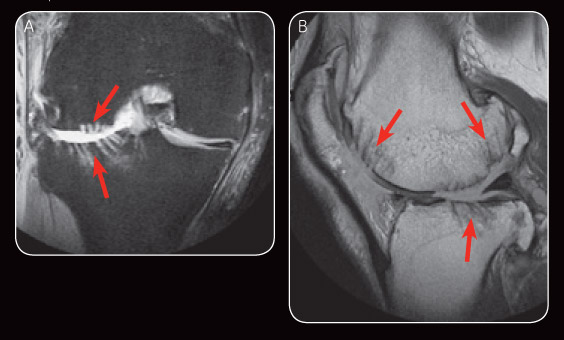

Fig. 2 Early post-operative MR images: PDFS (A) illustrates subchondral drilling at the lateral femoral condyle and lateral tibial plateau. Sagital PD (B) shows areas of subchondral drilling.

Fig. 3 Appearance on MR image at six-month follow-up demonstrates satisfactory repair cartilage and minimal subchondral oedema (A). Sagital PD at six-month follow-up also demonstrates satisfactory repair cartilage (B).